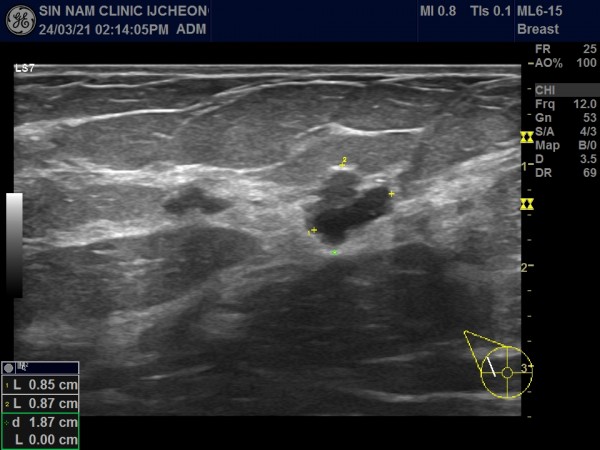

아래 사진 자료의 환자분은 50세 여성으로 국가검진으로 본원에 내원해주셨습니다.

유방촬영中 혹이 발견되어 초음파 검사를 시행하였습니다.

혹이 1.5cm 정도였습니다.

만져지거나 분비물이 나오는 증세는 없었습니다.

혹의 유두에 근접해 있고, 유관과 연결되어 있어 혈류가 증가된 소견이여서 유방암보다는 관내유두종의 가능성이 높아 대학병원으로 전원해 조직검사를 시행해서 관내유두종으로 진단받고 수술하셨습니다.